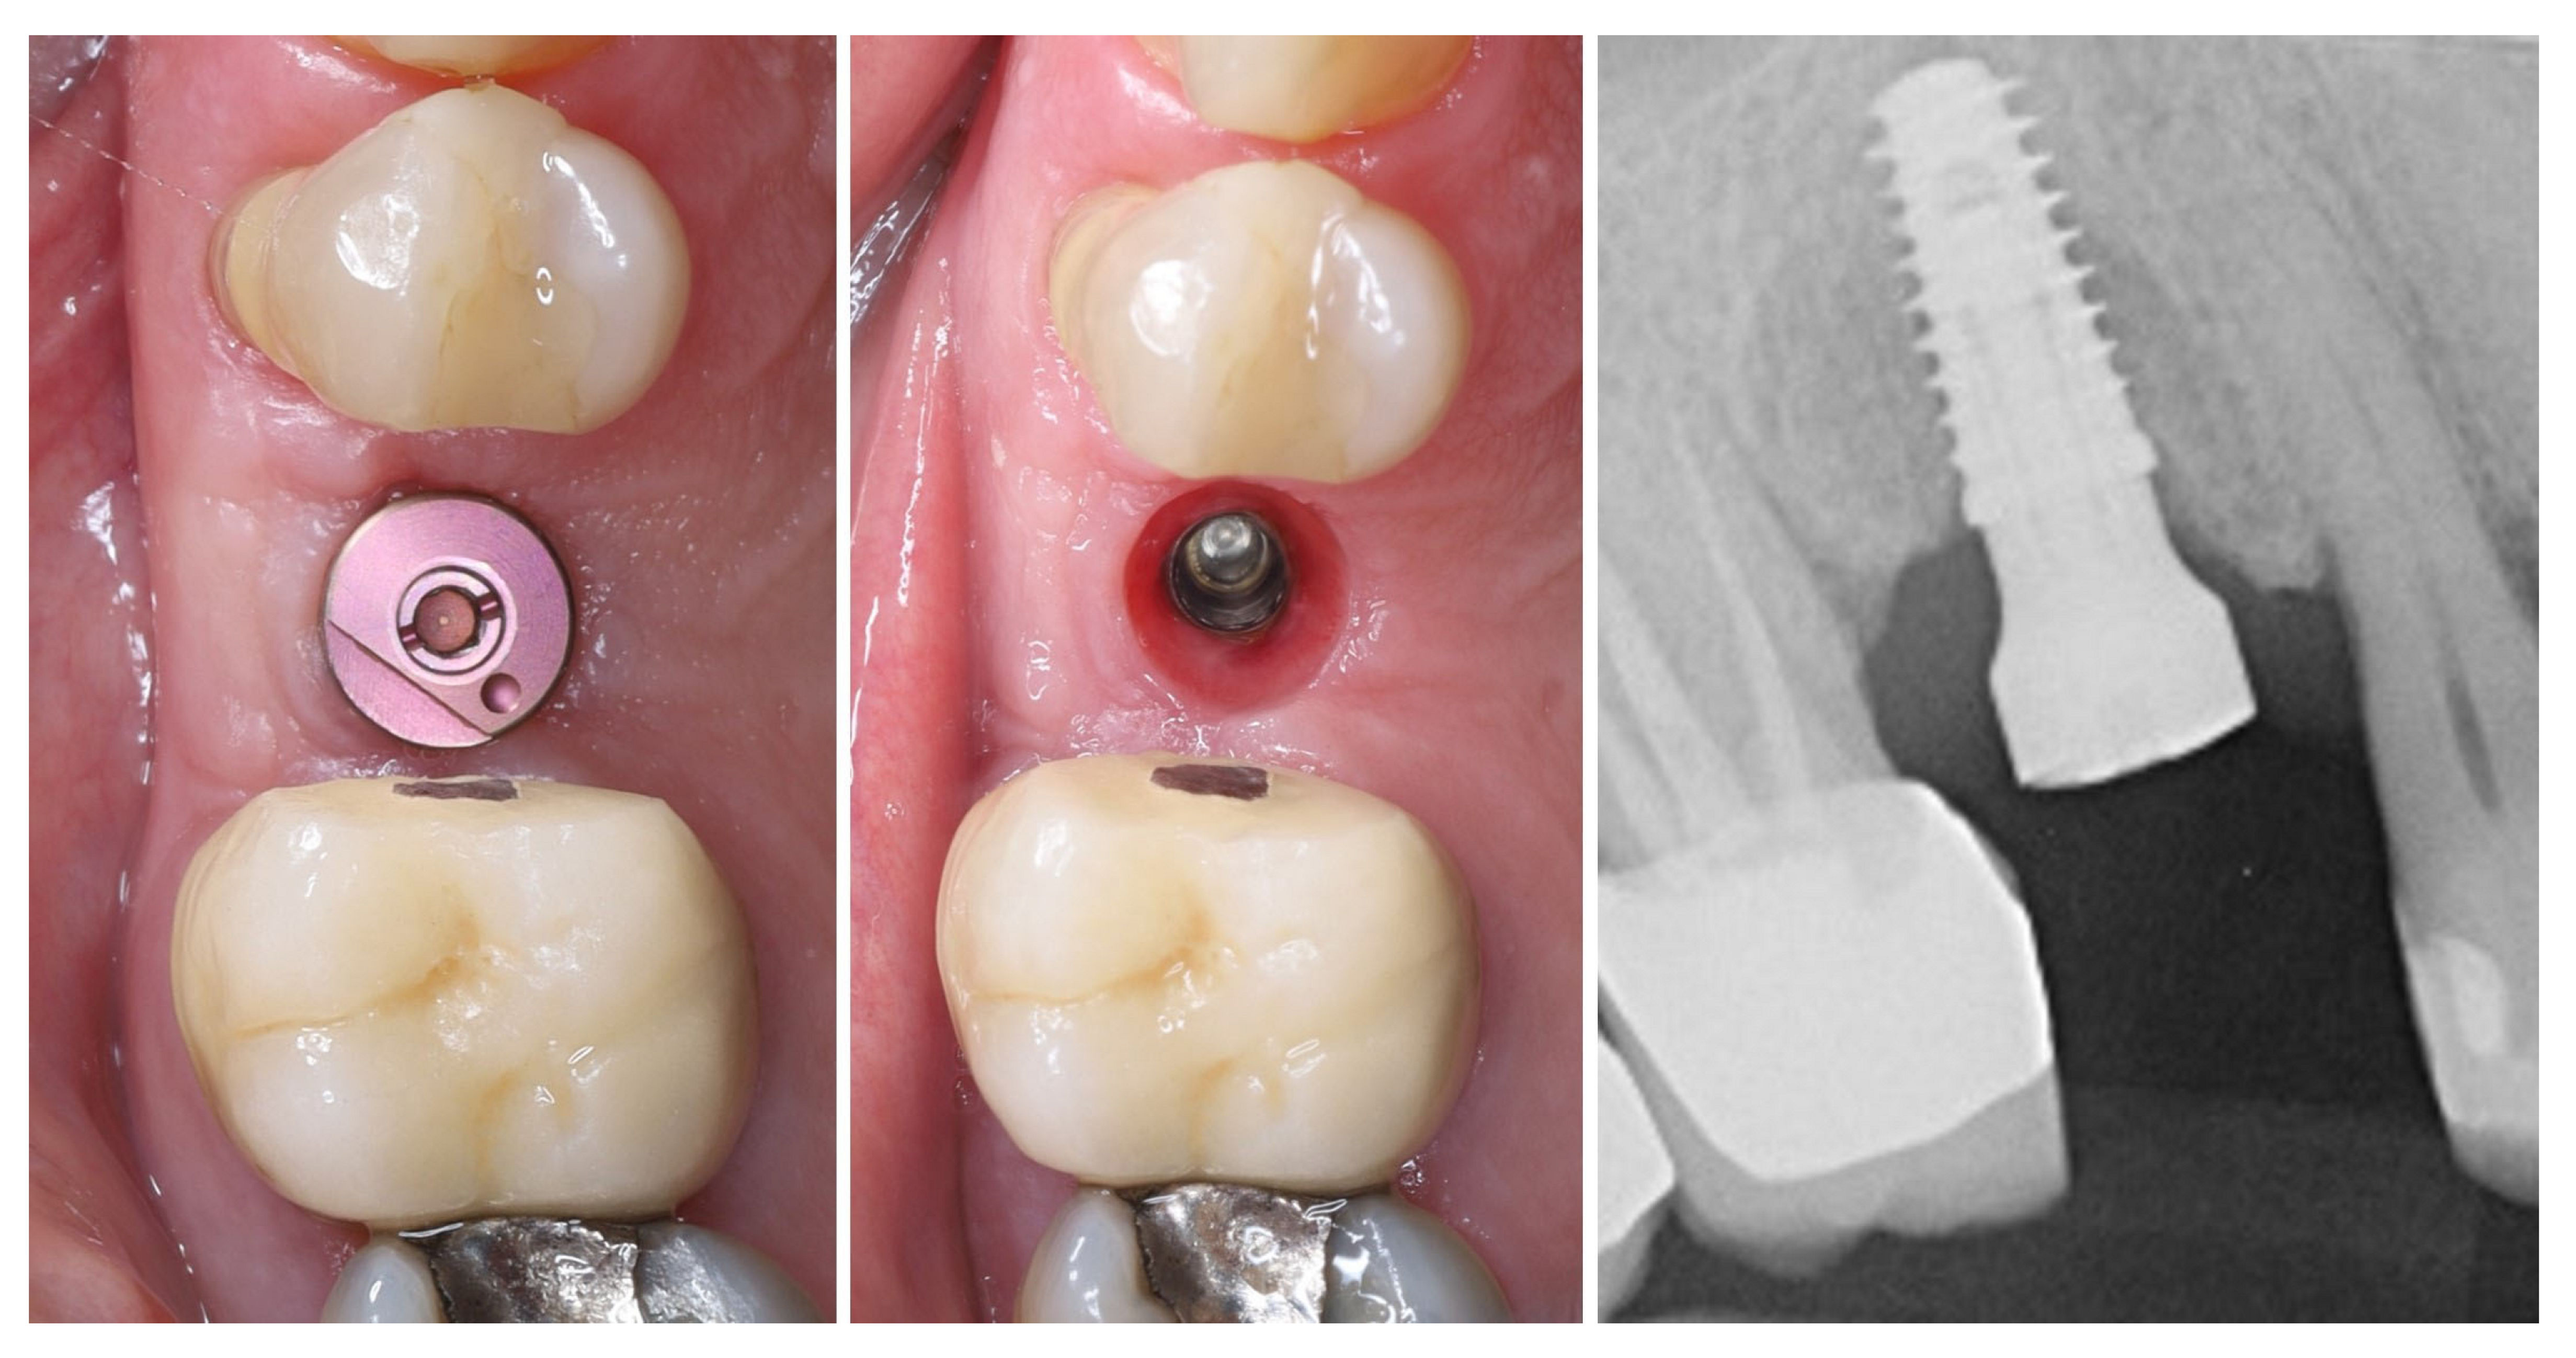

| Timepoint | Horizontal Thickness (mm) | Vertical Thickness (mm) | Clinical/Radiographic Findings | |

|---|---|---|---|---|

| 1 | Baseline (Day 0) | 2.3 | 2.4 | Initial thin buccal tissue |

| 2 | 2 weeks post-op | Uneventful healing, stable mucosal margin | ||

| 3 | 3 months post-op (with provisional) | 3.4 | 3.4 | Increased thickness, stable bone and mucosa |

| 4 | 4 months post-provisional | 3.5 | 3.6 | Stable peri-implant mucosa around provisional crown |

| 5 | 8 months post-op (final crown) | 3.5 | 4.1 | Final crown placed, harmonious soft tissue contours, and stable crestal bone |

| 6 | 14 months post-definitive | Long-term stability of soft tissue and crestal bone confirmed |